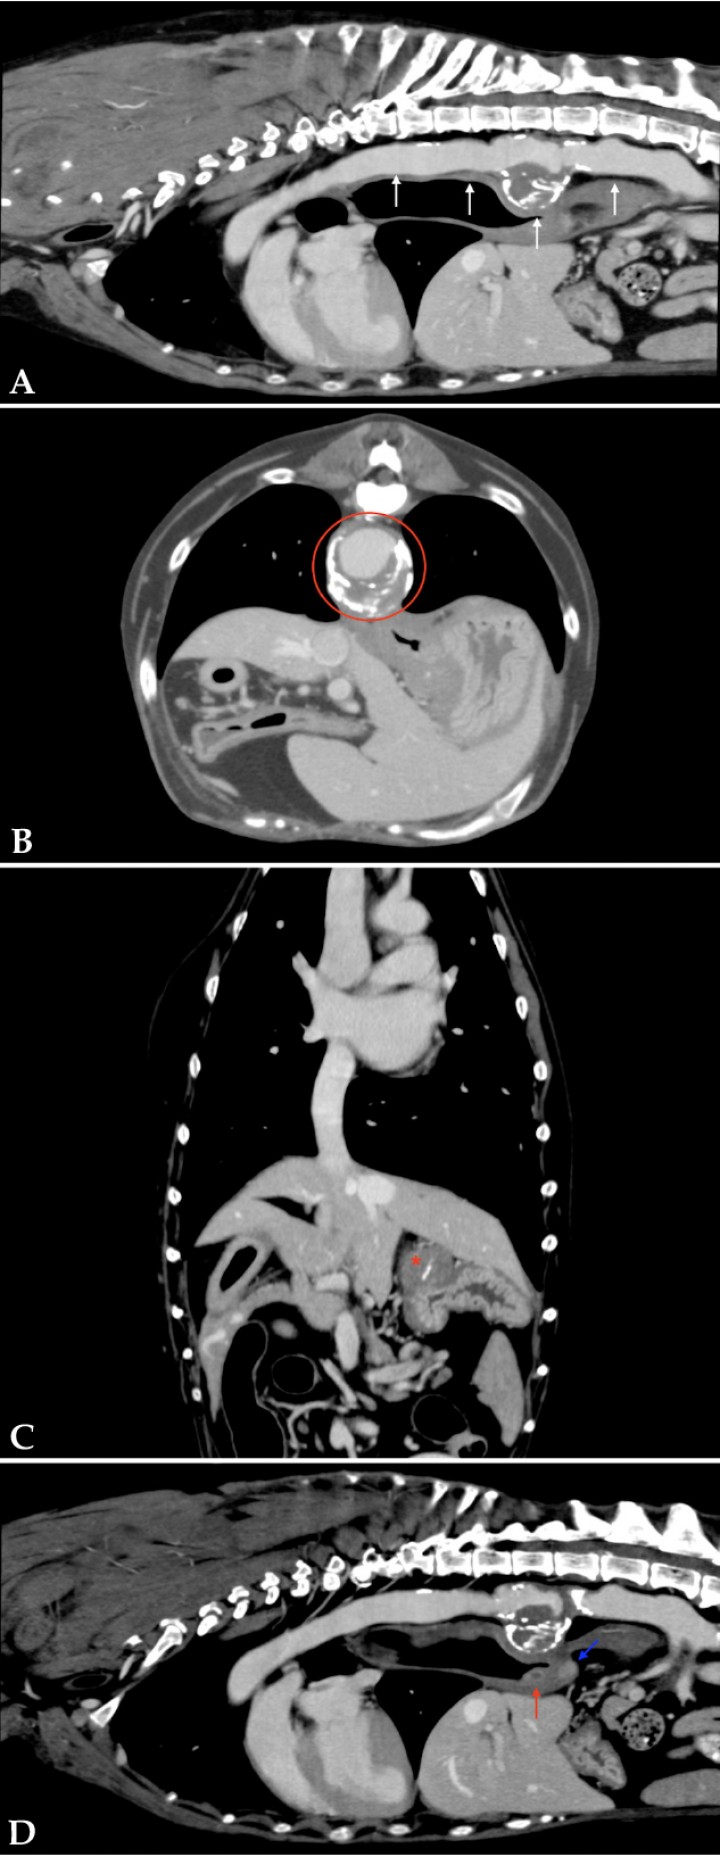

Se realizó una tomografía computarizada (TC) de tórax donde se observó dilatación de la aorta intratorácica caudal y de la aorta abdominal incluida en el estudio, con focos de mineralización distrófica en sus paredes. Además, se visualizó un aumento de espesor focal, circunferencial y asimétrico de su pared de 20 mm, ventral a T11. La aorta mostró una superficie irregular. Estos hallazgos confirmaron el diagnóstico de aneurisma aórtico.

En el aspecto craneomedial del fundus gástrico se observó una masa intramural isoatenuante de 23 mm, con márgenes irregulares y focos de mineralización distrófica, con captación pobre de contraste. También había dos nódulos intramurales e isoatenuantes, uno caudomedial al cardias de 10 mm con captación marcada de contraste y otro en pared medial esofágica, craneal al hiato, de 8 mm, con captación marcada de contraste en la periferia y pobre en su centro (Fig. 3).

<p style=\"text-align:justify\">Imágenes de TC de tórax en ventana tejido blando postcontraste. (<strong>A</strong>, <strong>D</strong>) Plano sagital. (<strong>B</strong>) Plano transversal. (<strong>C</strong>) Plano dorsal. Se observa dilatación de la aorta caudal y abdominal (flechas blancas) y dilatación circunferencial con halo hipoatenuante a nivel de T11 (área delimitada en rojo). Masa intramural craneomedial al fundus gástrico con mineralización distrófica (asterisco rojo). Lesión nodular localizada caudal y medial al cardias (flecha azul) y otra en la pared medial del esófago, craneal al hiato esofágico (flecha roja).</p>

Figura 3

Imágenes de TC de tórax en ventana tejido blando postcontraste. (A, D) Plano sagital. (B) Plano transversal. (C) Plano dorsal. Se observa dilatación de la aorta caudal y abdominal (flechas blancas) y dilatación circunferencial con halo hipoatenuante a nivel de T11 (área delimitada en rojo). Masa intramural craneomedial al fundus gástrico con mineralización distrófica (asterisco rojo). Lesión nodular localizada caudal y medial al cardias (flecha azul) y otra en la pared medial del esófago, craneal al hiato esofágico (flecha roja).

En el presente caso la TC con contraste evidenció la dilatación de la aorta intratorácica caudal rodeada por contenido hipoatenuante que no captaba contraste sugerente de antigua hemorragia, lo cual indicaba la ruptura y cronicidad del proceso.